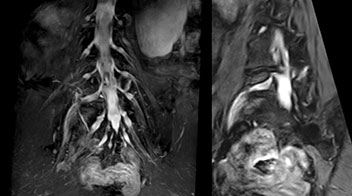

At Northern Fukushima Medical Center in Japan, excellent MRI visualization of nerves helps support confident diagnoses and informs surgical treatment decisions for patients with lower limb symptoms. MRI technologist Tanji and orthopedic surgeon Dr. Yabuki share how direct nerve visualization with the 3D NerveVIEW method adds information when diagnosing atypical herniations. The additional insights changed their way of working and benefit their patient care, as illustrated by some clinical examples.

“In patients with lower extremity neurological symptoms, NerveVIEW helps us to determine the disease matching the patient’s symptoms by directly visualizing the nerves. We use the sequence mainly, when there is suspicion of intraforaminal stenosis, extraforaminal stenosis or lateral disc herniation, which is often based on routine T2- and T1-weighted images. Additionally, the excellent depiction of the course of nerves makes NerveVIEW a good navigator when applying treatment such as block therapy or surgery.”

Northern Fukushima Medical Center (NFMC) Imaging Center uses the 3D NerveVIEW sequence for performing MR neurography, particularly in patients with pain and weakness in the lower limb. “It is included in about 20% of the approximately 150 lumbar spine MRI exams each month at NFMC, and can help us to determine if structures are impinging on the nerves,” says Hajime Tanji, RT, MRI technologist at NFMC.

“In such case, we would then browse through axial T2-weighted MR images slice by slice and mentally reconstruct the actual situation based on both radiculography and MRI. Fortunately, NerveVIEW can now very well show nerve courses and presence of nerve compression or edema in one single image series.” “We have often seen NerveVIEW directly depict details of the nerve compression that were not observed by radiculography. Therefore, we think that with NerveVIEW we can reduce the number of invasive examinations, especially for some patients with lumbar plexus symptoms.”

“Before NerveVIEW, diagnosis by MRI alone was sometimes difficult, unless there was a strong suspicion based on clinical symptoms,” says Shoji Yabuki, MD, DMSc, Orthopedic surgeon at Fukushima Medical University School of Medicine. “This is why we routinely perform selective lumbosacral radiculography (nerve root block) and x-ray in such cases. However, radiculography can only depict nerves as far as the contrast agent reaches. When a nerve is distorted by compression, the contrast agent will not pass through this compressed area, preventing us from evaluating the full nerve compression.”

The key concept in MR neurography, Dr. Yabuki stresses, is the ability to directly visualize spinal nerves, versus inferring the presence of pathology indirectly. “Before NerveVIEW, we estimated compression of the nerve by looking for the presence or absence of fat signal on other MR images,” he says.

“For example, in sagittal images, when the presence of fat is observed in the intervertebral foramen, it suggests that there is a margin around the nerve. Similarly, the absence of fat indicates that the nerve is being compressed. So, we used to deduce nerve compression indirectly. With NerveVIEW, however, we can observe the condition of the nerves directly, regardless of the presence or absence of fat. We always prefer such direct observation of anatomy over having to make an inference about it.”